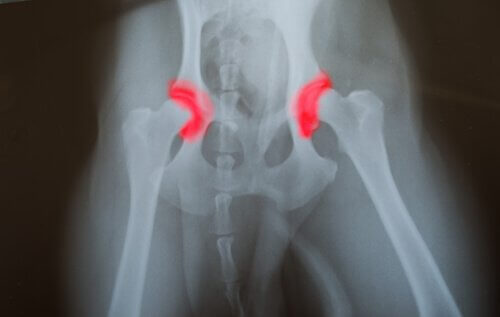

Eğer bir köpek yavrusu aşırı beslenirse kilo alacak ve tavsiye edilenden daha hızlı bir şekilde büyüyecektir. Bu, iskeletine çok fazla baskı uygular ve aşağıdaki hastalıklara neden olabilir:

- Osteokondroz

- Kalça displazisi

- Dirsek kemiğinin parçalanması ve ayrılması

1974 yılında yapılan bir çalışmada protein, fosfor ve kalorisi yüksek diyetleri uygulayan 12 çift Danua cinsi köpek analiz edildi. Daha önce belirtilen hastalıklar, bu diyetlerle beslenen köpeklerde daha yaygın olarak gözlemlendi.

Dengesiz bir beslenme düzeni olan büyük köpeklerle karşılaştırıldığında, dengeli bir beslenmesi olan köpekler aşırı büyümeyle ilişkilendirilen daha az hastalığa sahip oldu. Kalça displazisi, büyük ve aşırı beslenmiş köpeklerde en sık görülen hastalıklardan biriydi.